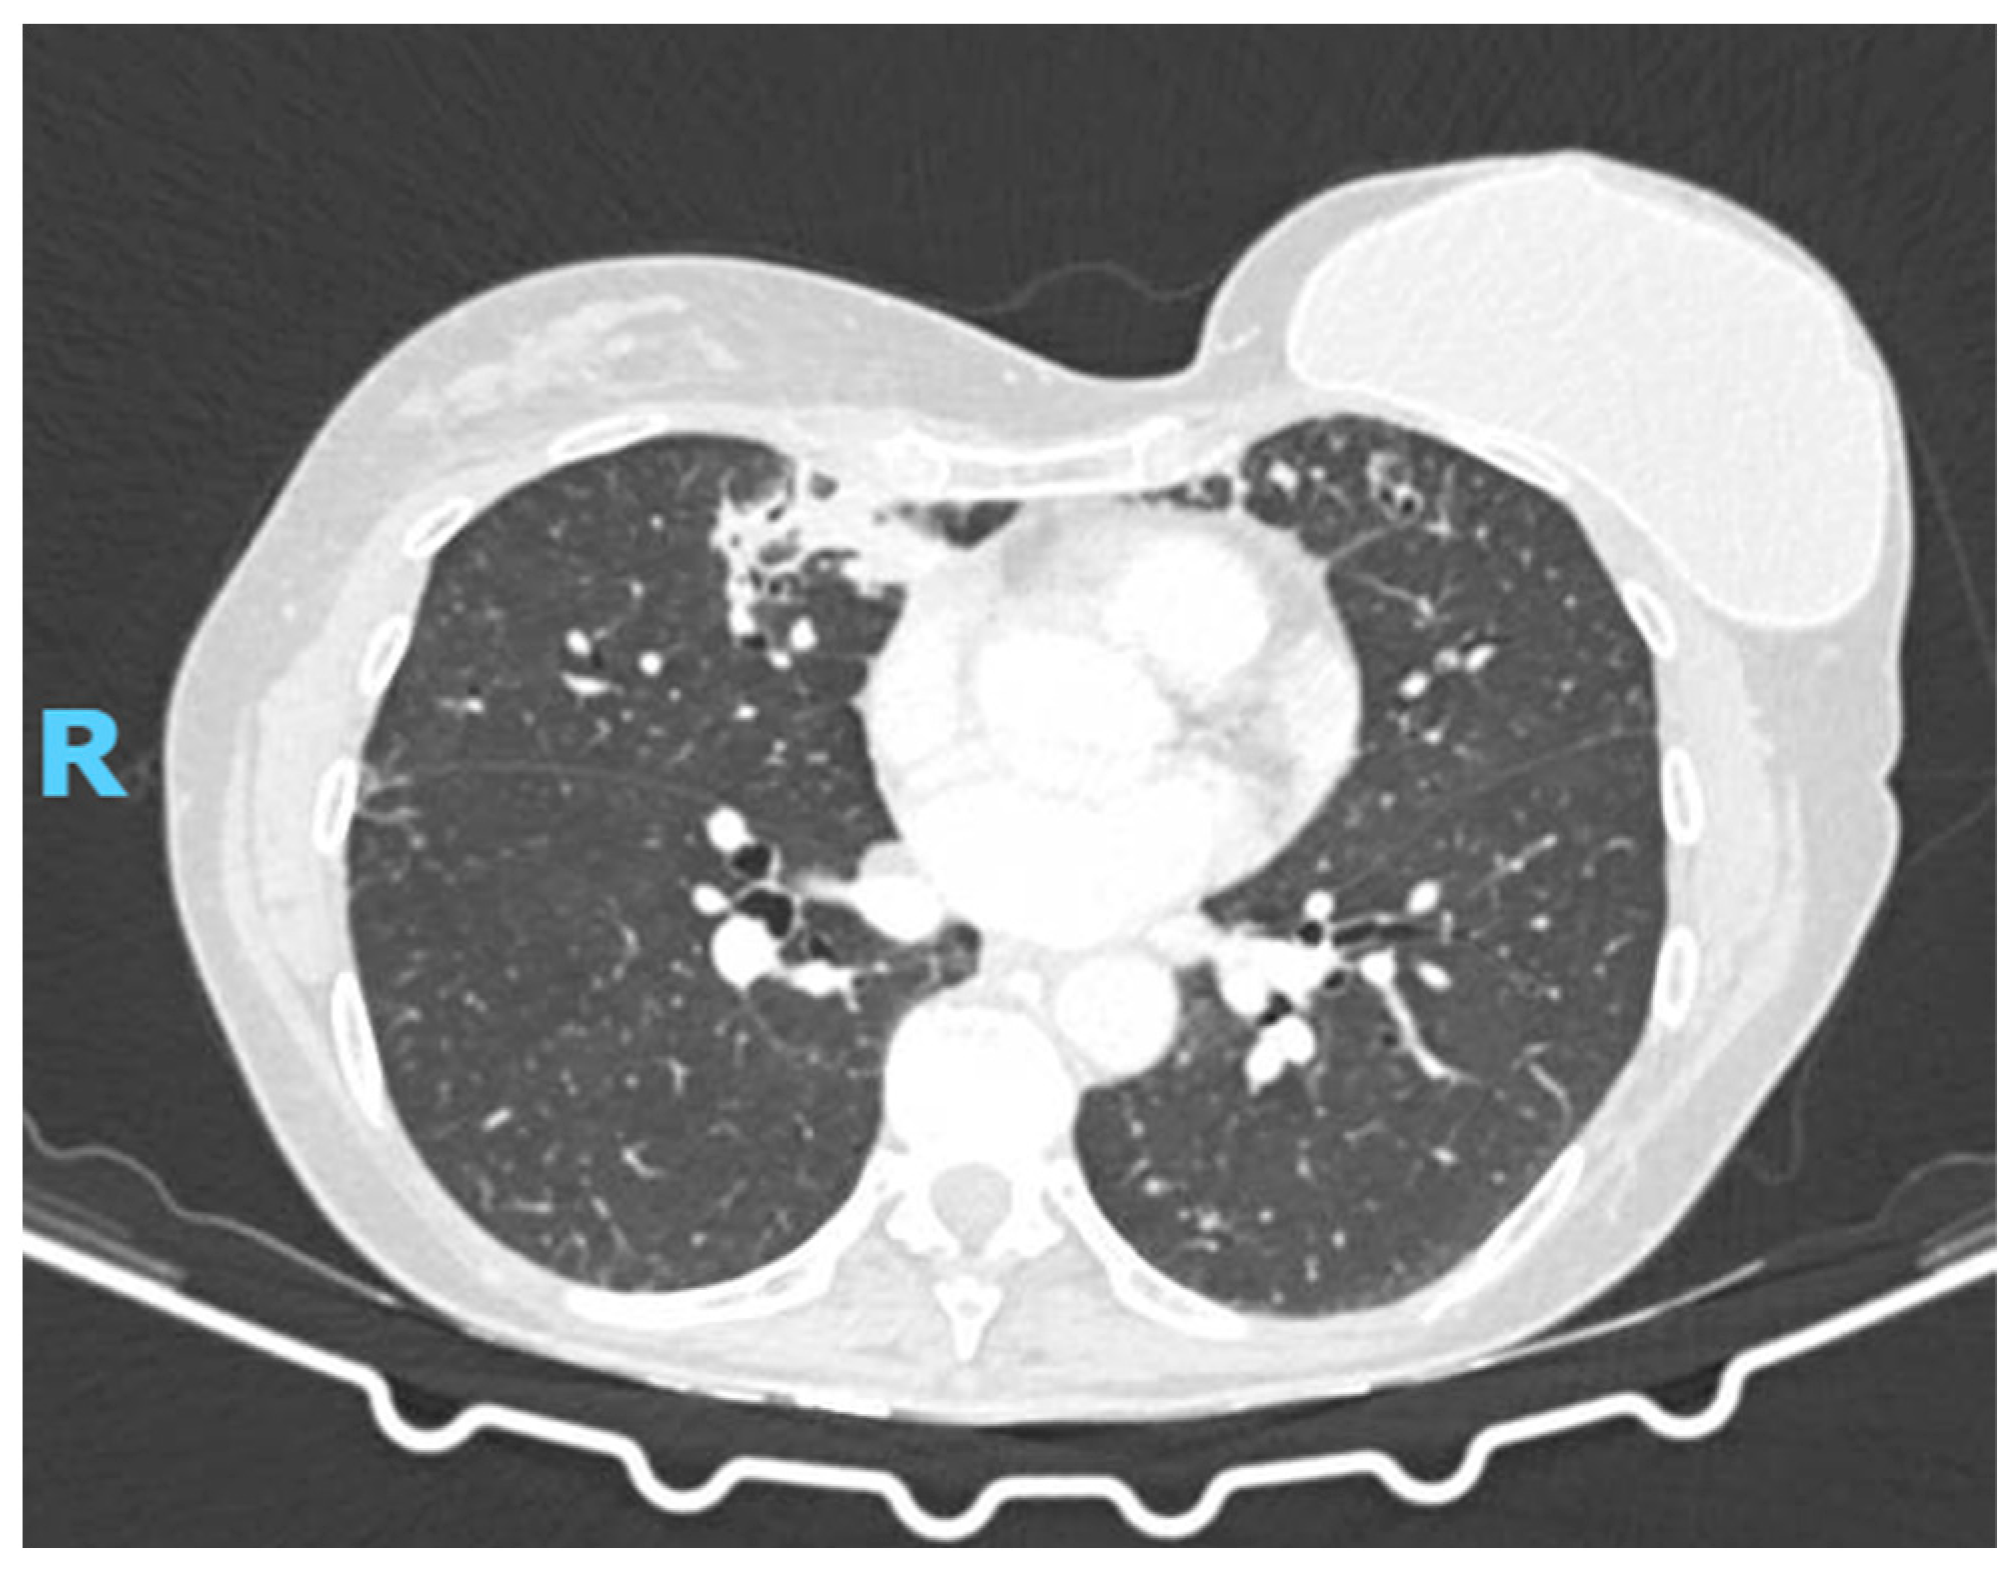

2. Case Presentation

2.2. Diagnostic Studies